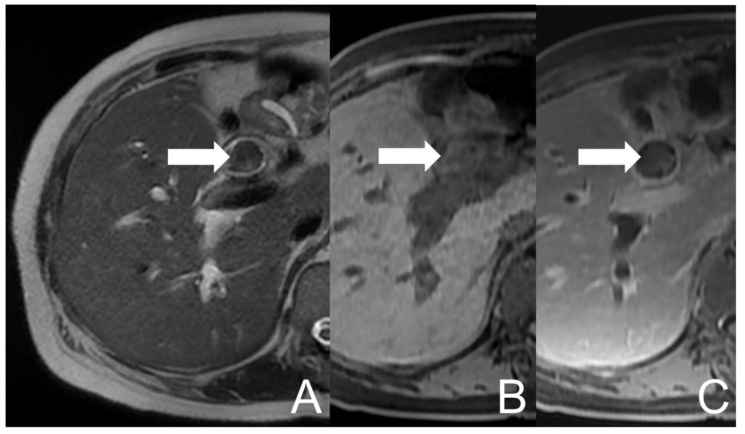

She suffered from abdominal pain in the right upper quadrant along with right flank and back discomfort for 2–3 months. The symptoms exacerbated and she went to a local hospital where abdominal computed tomography (CT) revealed dilatation over IHD and CBD in the presence of stones. Acute cholangitis was impressed and antibiotics were prescribed. The symptoms of fatigue, poor appetite, jaundice, low-grade fever and right epigastric pain developed again in spite of therapy. She visited our Emergency Department for medical help, where cholangitis was suspected. She was subsequently admitted for further evaluation and management. Endoscopic retrograde cholangiopancreatography (ERCP) was performed which showed hemobilia in the presence of lots of tissue material and blood clots within CBD. Some tissue material was extracted and sent to pathologic examination. Magnetic resonance cholangiopancreatography (MRCP) was arranged, which revealed dilatation and mild increase in wall thickness and enhancement of the biliary tract. A lobulated lesion in CHD and CBD was also found, extending to the confluence (about 9.8 cm × 1.9 cm), with heterogeneous signal intensities on the T1-weighted image (mainly high signal intensity) and T2-weighted image (mainly low signal intensity). Some equivocal enhancing foci of the lesion were suspected (Figure 1). The impression of cholangitis could be compatible, accompanied with possible debris, hematoma or neoplasm. The pathology reported an admixture of blood clots, fibrin and inflammatory cells. Aggregation of histiocytes and scanty pancreatobiliary-type epithelium with bland cytologic features was noted whilst there was no evidence of malignancy. A blood culture yielded Escherichia coli. Empirical antibiotics were prescribed and the symptoms subsided. The patient was discharged under a stable condition.